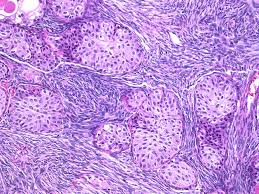

-- digital pathology can be used in education, case reviews and QA; can be Whole slide imaged (WSI) or static (ie gross camera, scope cams) imaged

- telepathology involves common points of use (grossing, intraop dx, histo), equipment (camera/scanners, computers c software, comm devices (phones), and certain benefits (time) and challenges (cannot see specimen)